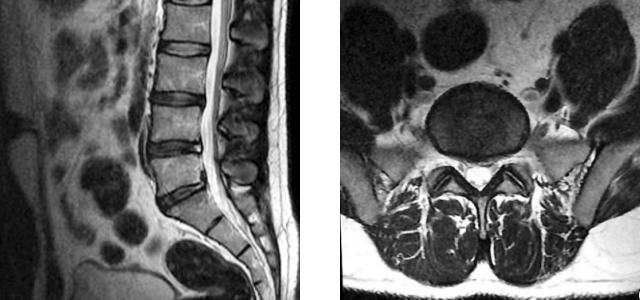

MRI shows herniation

The following morning Jane is able to have the MRI done and returns to see Dr. Kim. Dr. Kim reviews the MRI imaging with Jane, telling her she sees the expected bulge in the spinal disc that is pinching the sciatic nerve. This diagnosis confirms the cause of Jane’s lower back and leg pain. The technical term for this type of spinal disc herniation is an L5-S1 herniated nucleus pulposus. Dr. Kim refers Jane to a physical therapist, telling Jane that the therapy and pain reliever are the best ways to speed her recovery. After the ibuprofen regimen Jane was prescribed during her previous appointment has ended, Jane is to take two ibuprofen 200 mg over the counter as needed up to three times a day. She may stop taking ibuprofen completely as soon as her pain stops.

In a nutshell: Imaging is not called for in the circumstances surrounding Jane’s initial visit. Sudden worsening of her pain is a reason for the need for imaging. MRI typically does a nice job of showing disc herniation. X-radiography does not, but is done to rule out other dangerous conditions that could be contributing to Jane’s symptoms. In Jane’s case the MRI is done first, and only if the MRI does not show the reason for her pain will an x-ray be necessary.

Imaging is not indicated in acute lower back pain or sciatica. One indication for MRIs and x-rays is sciatica that does not resolve in six weeks. An MRI becomes indicated for Jane when the condition suddenly worsened following the misstep on the stairs. Imaging after symptoms subside is contraindicated. It was done in this case only because Jane was in a research study which included an MRI as part of the study. The physical therapist told her of a study that matched her symptoms, and Jane decided she would like to enroll.

In asymptomatic individuals, about 20% will have findings of disc herniation, and about 30% will show a bulging disc. This lack of specificity of MRI as a tool utilized to diagnose these conditions makes an MRI unsuited to routine diagnostic use for lower back pain problems. There would be an unacceptable number of false positives. The physical exam is adequate for diagnosis except in cases where sciatica lasts 6 weeks, or where pain, numbness, or other indications make an MRI needed. At this point imaging is necessary to see more precisely what the patient’s situation is in the event there is a condition that requires emergency treatment, or the imaging is used to guide surgical intervention decisions.